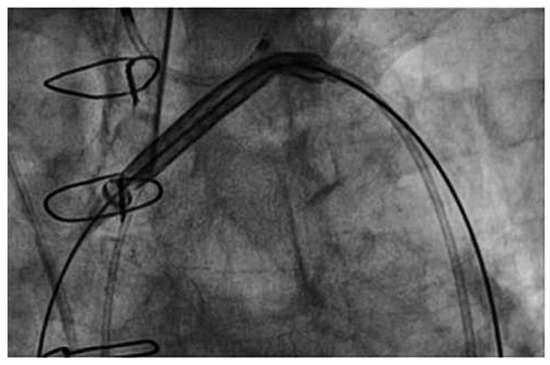

Embrella

The Embrella device (Edwards Lifesciences Ltd., Irvine, CA, USA) is introduced either through the right radial or brachial artery. The concept of the device is to deflect rather than to capture emboli. Proof-of-concept was shown in the year 2010 in a first-in-human study [16]. The study confirmed the simple handling of the device, with an additional procedural time of only 13 minutes. Whether it is an atraumatic and effective device needs further investigation in a large trial. The Embrella is an umbrella-like device that consists of 2 polyurethane membranes mounted on a nitinol frame. The device is attached to a 0.035-inch nitinol delivery cable (Figure 1A). It can be folded, sheathed and loaded into a 6F long delivery sheath, which itself is placed over the right radial or brachial artery into the ascending aorta. Then the device consisting of two petals is released from the sheath. It is pulled back and positioned at the outer curvature of the aortic arch such that the petals cover the left carotid and the innominate artery (Figure 1B). In some patients it will further (partially) cover the left subclavian artery. The polyurethane membrane has 100-µm pores to ensure proper blood circulation downstream of the device.

Sitting at the outer curvature of the aortic arch, the device does not interfere with the TAVI procedures, and in particular there is no interference with the large valve delivery system. Once the procedure is terminated, the device is re-sheathed using the 6F delivery sheath.

Figure 1. The Embrella device. (A)The device consists of two petals and a delivery cable. (Courtesy of Edwards Lifesciences Ltd., Irvine, CA, USA.). (B) Once positioned at the outer curvature of the aortic arch, a contrast injection through the delivery sheath confirms proper placement. Note that the two petals of the device cover the brachiocephalic trunk and the left carotid artery. Red arrow = brachiocephalic trunk; red star = aortic lumen.